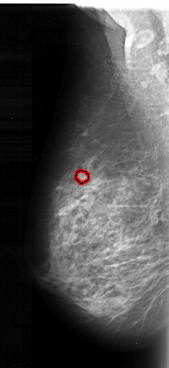

FILE: A_1097_1.LEFT_MLO.OVERLAY

TOTAL_ABNORMALITIES 1

ABNORMALITY 1

LESION_TYPE CALCIFICATION TYPE PLEOMORPHIC DISTRIBUTION CLUSTERED

ASSESSMENT 4

SUBTLETY 4

PATHOLOGY MALIGNANT

TOTAL_OUTLINES 1

BOUNDARY